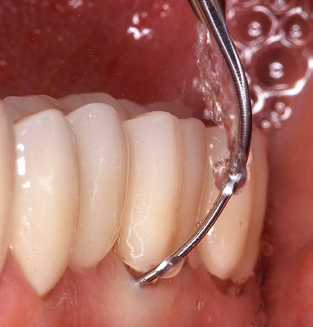

The current working concept for SPT

Good illumination of the working field facilitates the process considerably. The system used by the authors achieves this thanks to a 5x LED ring integrated in the handpiece. Naturally, a range of working tips for different indications is also offered. A straight, universally employable tip is the basic instrument required for machine cleaning of natural teeth (Fig. 5a and b). Curved tips, which allow access to exposed furcations, are also available for hard-to-reach areas in the posterior region (Fig. 6).